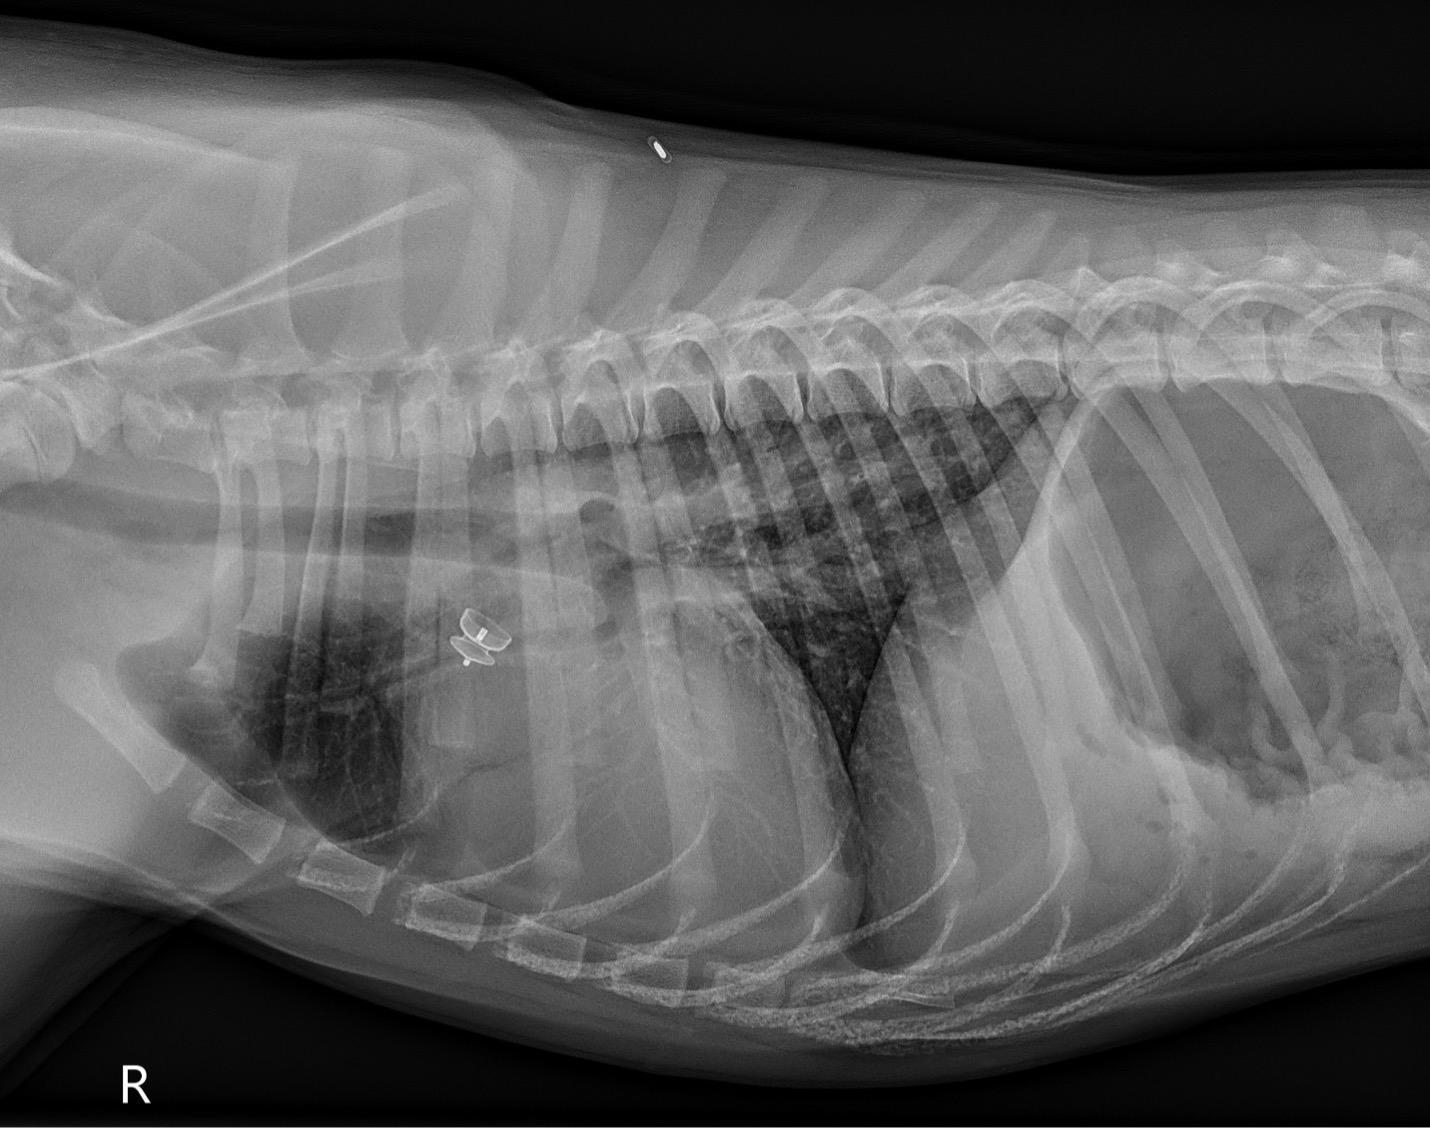

Post-operative thoracic radiographs (Figure 3): Improved cardiomegaly with reduction in pulmonary vascular overcirculation. Similar mild diffuse bronchial pattern. ACDO device in native shape in the ductus arteriosus.

PICTURE: Figure 3: Post-operative right lateral thoracic radiograph.